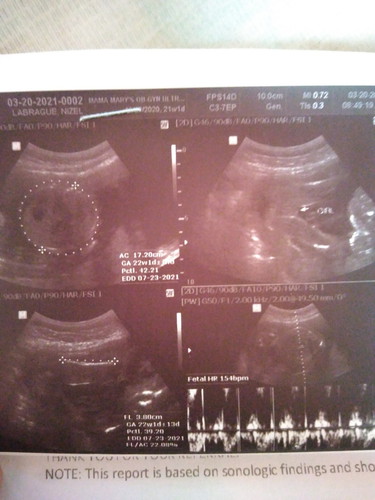

Hey! Mommies I am 23 weeks pregnant ask lang po ako kung pwede na magpahilot na transverse baby ko

Ako mamshie sa last utz ko CAS 21weeks before BREECH din😔 pero sabi ni OB iikot pa naman daw sya. On my opinion mas TAKOT ako sa mga hilot🥺 mahirap na auko mag take a risk.

ako breech din ako before, nung 22 weeks ako pero hindi ako ngpahilot..umiikot din naman si baby, now i'm 34weeks, nasa tamang position na sya..cephalic anterior😀😀